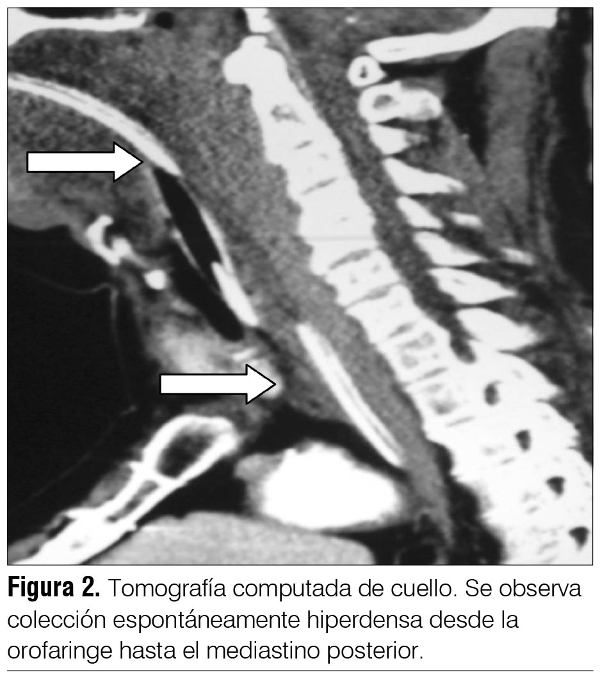

Se realiza tomografía computada (TC) que informa (figuras 1 y 2): en cuello eje visceral del cuello bien centrado. A nivel prevertebral se observa colección espontáneamente hiperdensa desde la orofaringe hasta el mediastino posterior compatible con hematoma. No neumomediastino ni enfisema subcutáneo. Vasos mediastinales y troncos supraaórticos permeables y de calibre habitual. No se observa flat intimal. En cráneo, sin alteraciones de la densidad del parénquima, estructuras de la línea media bien centradas. Resto normal.

Nuestro paciente desarrolló un hematoma retrofaríngeo por accidente de tránsito como conductor de moto contra moto, sin casco, con impacto a nivel de la arcada superciliar izquierda, sin traumatismos en otros territorios, instalando en la primera hora del accidente dificultad respiratoria dada por polipnea y estridor. La TC de cuello y tórax evidencia la presencia de una colección espontáneamente hiperdensa a nivel prevertebral que abarca desde la orofaringe hasta el mediastino posterior compatible con un hematoma.